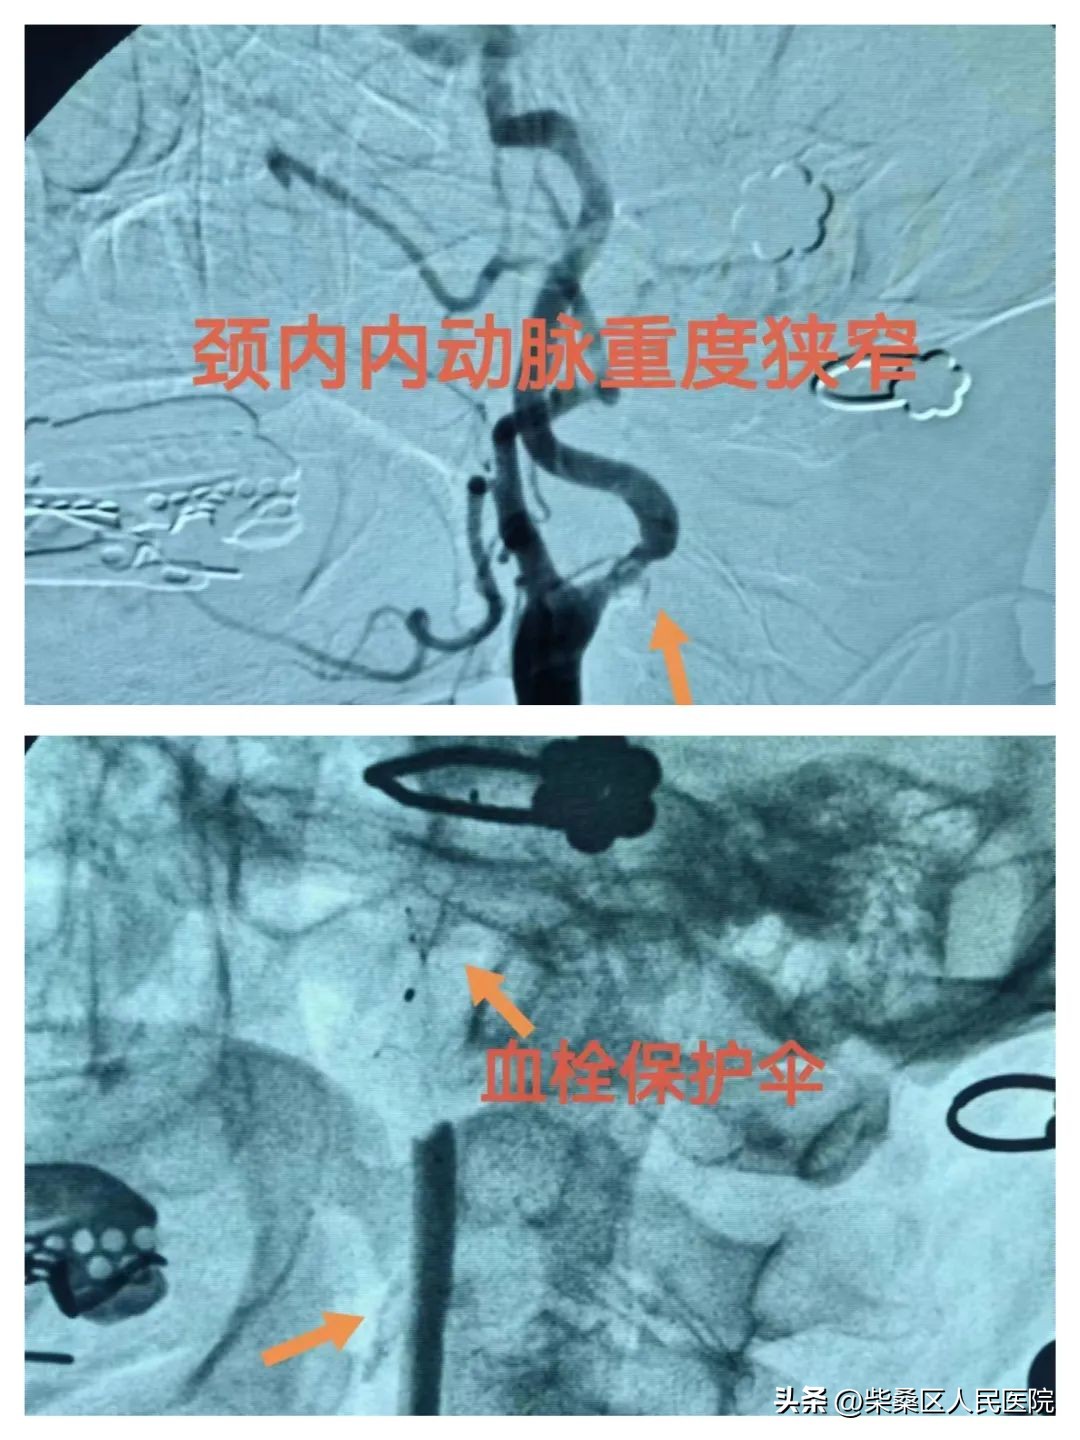

神经内科:颈动脉狭窄球囊扩张+支架植入术

患者女性,68岁,因突发头晕3天入院,诊断:短暂性脑缺血发作。造影提示:右侧颈内动脉重度狭窄。考虑此次发病与血管重度狭窄有关,有进一步发展加重并发脑梗死风险,有介入手术指征,予以介入下行颈动脉狭窄球囊扩张+支架植入术,术后患者头晕较前明显缓解。